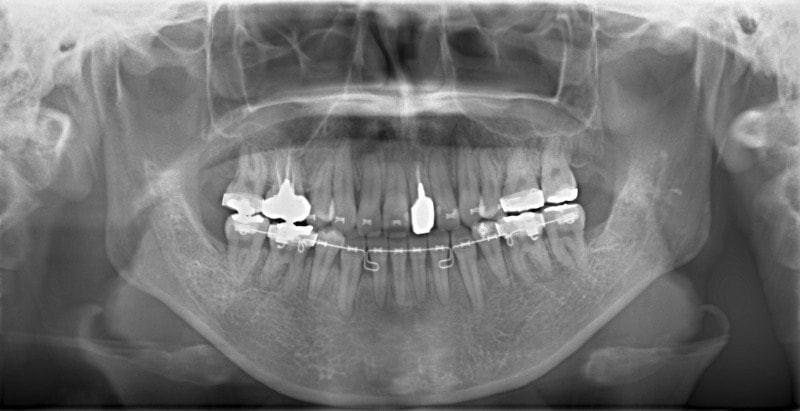

治療開始から約1年後

歯根のパラレリング(平行性)が獲得されております。

下顎8番は、両側抜歯済みです。

顎位は良好な状態です。